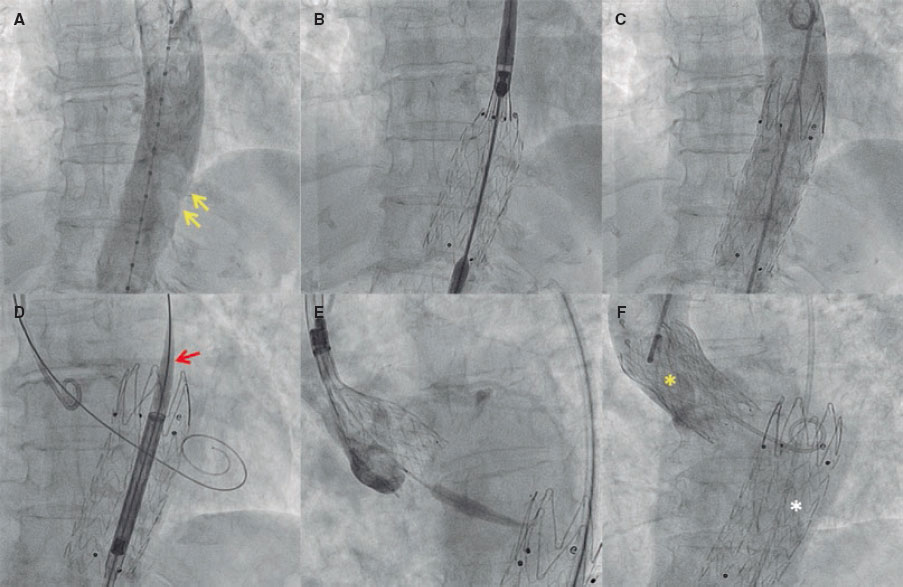

To reduce the risk of aortic plaque-related complications during TAVI—particularly the risk of embolization (figure 2A, arrows)—we planned a staged strategy consisting of aortic stent-graft implantation followed by TAVI. Via a single 18-Fr transfemoral access, we implanted an 85 mm × 32 mm Endurant II covered stent-graft system (Medtronic, United States) (figure 2B-C and figure 2F, white asterisk). Afterwards, we advanced the TAVI delivery system through the stent-graft uneventfully (figure 2D, arrow), and implanted a 26-mm self-expanding Evolut FX+ valve (Medtronic, United States) (figure 2E-F, yellow asterisk), with no significant residual gradient and only mild paravalvular regurgitation on angiography. The patient was discharged without complications. Functional class improved, and transthoracic echocardiography confirmed the normal functioning of the TAVI at the 1-month follow-up.

Figure 2.